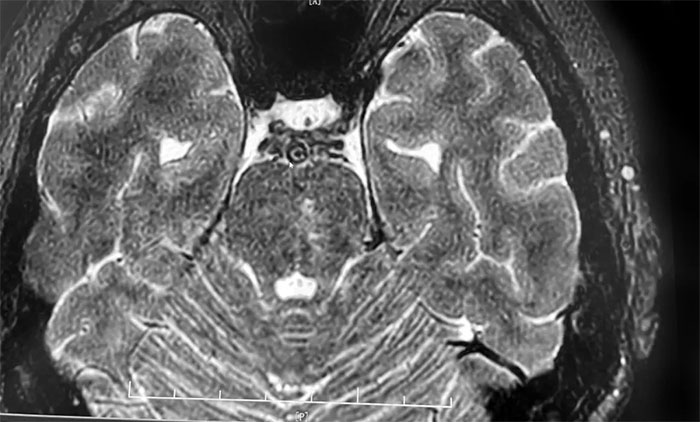

头颅MRI+SWI+DTI提示脑干梗塞,双侧桥臂变性;双侧放射冠区、额顶叶散在腔梗、缺血灶。基底动脉HRMR平扫+增强提示基底动脉管壁增厚伴重度狭窄。头颅CTP显示,右侧顶枕颞叶局部脑组织灌注较对侧稍减低。DSA提示基底动脉中段重度狭窄。

▲ 脑干梗塞